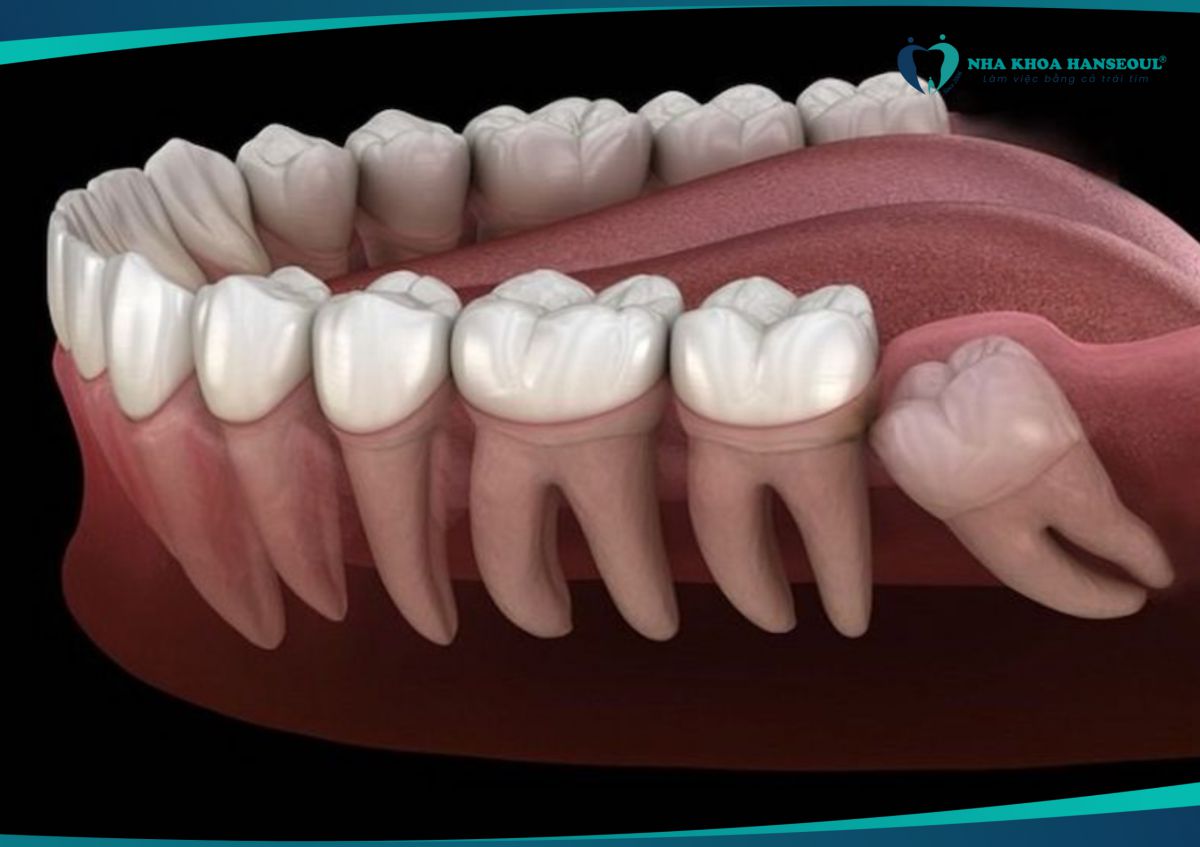

4 Ảnh hưởng đến răng số 7

- Răng khôn mọc lệch có thể đẩy vào răng số 7, gây sâu răng, lung lay hoặc thậm chí mất răng vĩnh viễn.

- Nếu không điều trị sớm, bạn có thể phải nhổ cả hai răng.

7 Gây xô lệch cả hàm răng

- Răng khôn mọc lệch có thể làm thay đổi cấu trúc hàm, khiến các răng khác bị xô lệch, ảnh hưởng đến thẩm mỹ và chức năng nhai.